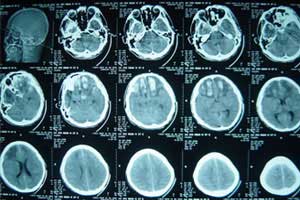

颅骨修补术是针对脑外伤导致头颅缺损而对头颅进行修补的一种脑外科常见的手术。

颅骨修补术可以解决缺损区没有对脑组织的有效保护、供血障碍、脑脊液循环异常等问题,还需要解决外形修复整形的问题。

CT三维重建技术的数字化颅骨塑形技术是对颅骨修补手术的一次革命性的进步,CT三维重建是根据患者颅骨缺损的状况,模拟颅骨的自然形态,经过CT的数据处理、医学的三维重建、颅骨自然曲面的表面绘制、计算机图形图像的辅助设计和钛金属的数字制造等5项程序,利用三维CT检查结果,为患者精确地设计预制出个性化的修补缺损的钛合金头骨。